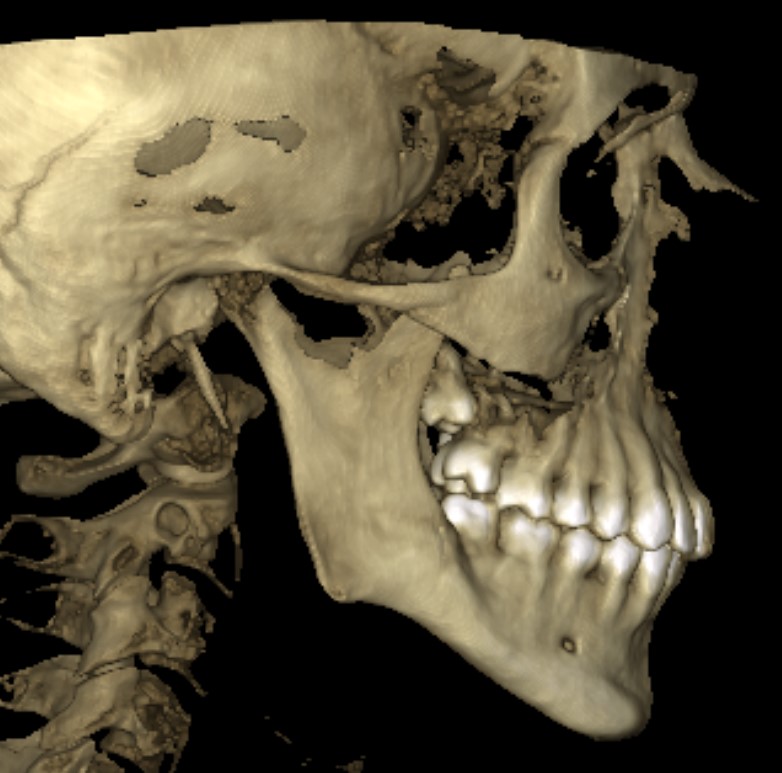

CBCT (Front + Side) + OPG (Old Before & New After braces) (need decompensation)

My Analysis (Based on CBCT):

- Gonial Angle: 131.8°

- Face Type: High divergence, nasolabial folds, poor midface & infraorbital support)

- Bimax (BSSO + Lefort 1) with CCW Rotation: I need to close that 132° angle and get projection.

- Jaw/Angles: I definitely lack bone mass here too. I'm considering custom jaw implants (wraparound or angles), but I’m worried about two things: 1) Is it even possible to do Bimax + Midface + Jaw implants in a single op? 2) The budget might explode.

- Genioplasty: Undecided. If the CCW rotation provides enough projection, I might skip it, but idk tbh.